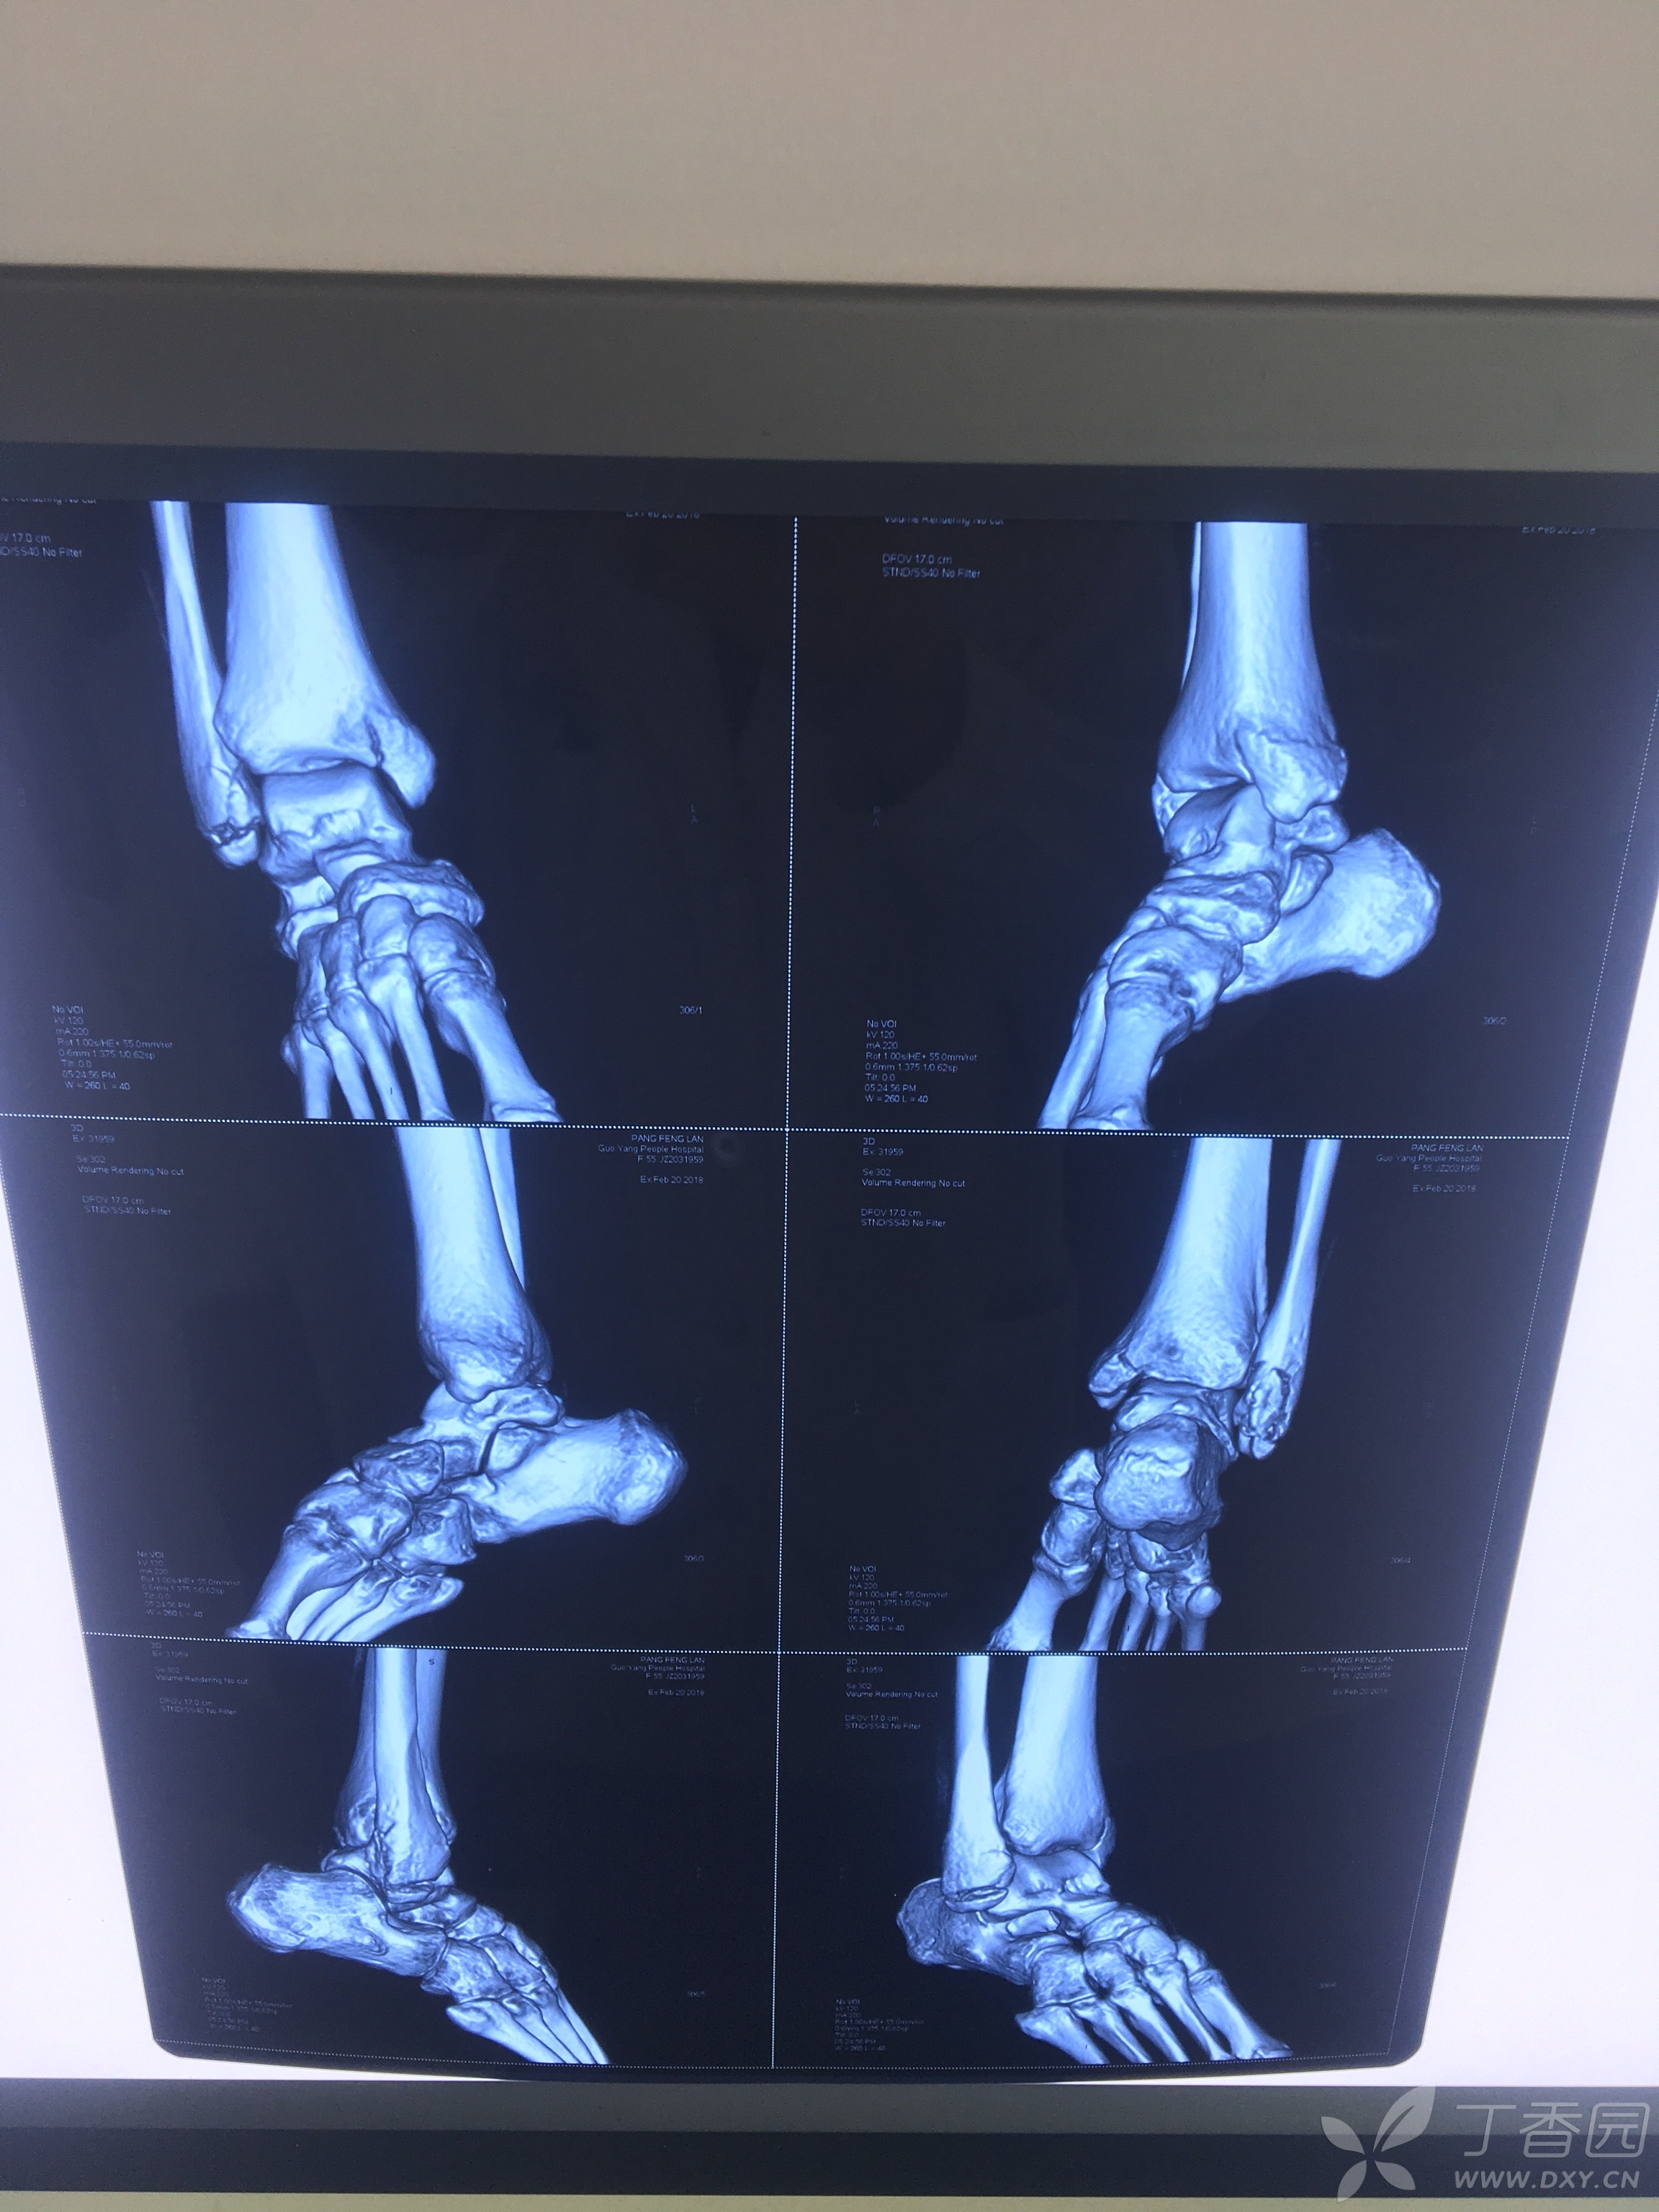

内外踝骨折!制定手术方案!大家讨论!

"张氏中医正骨"再次成功手法复位一例严重内外踝骨折